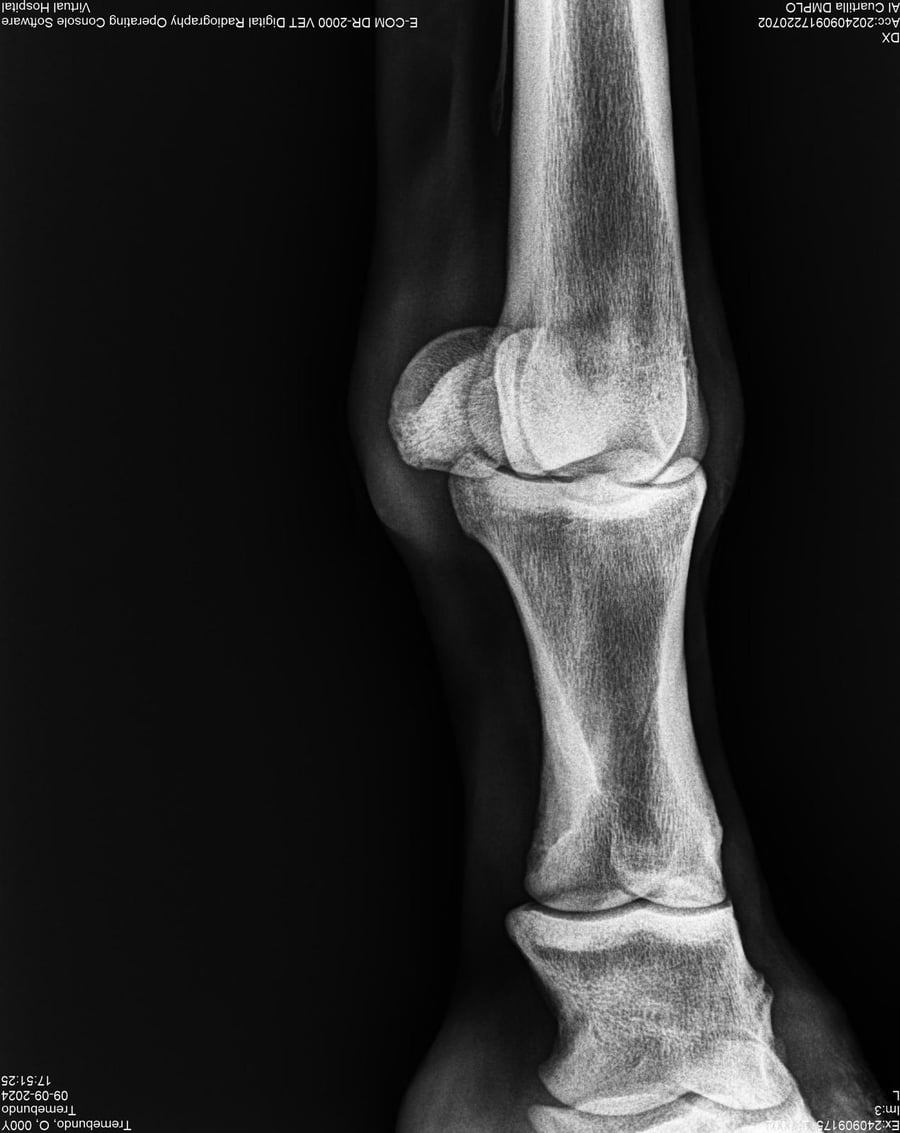

LOTE 37, TREMEBUNDO

Ficha del Lote

Identificador: #291140-

Generacion 2022